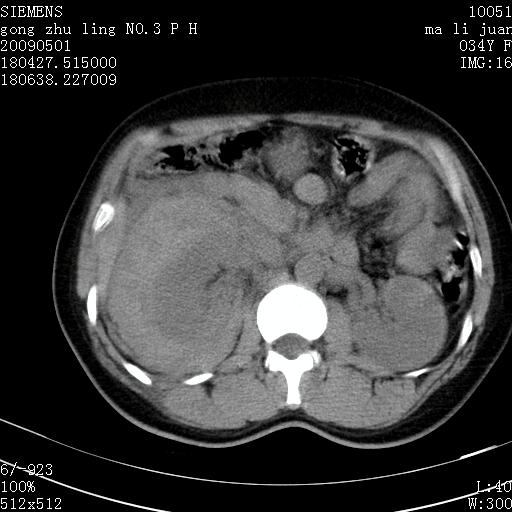

标题: CT19733:右肾碎裂 [打印本页]

标题: CT19733:右肾碎裂

青年女性,骑摩托车摔伤。

右肾碎裂伤,包膜下血肿。

术中仅见右肾碎裂,肾蒂血管未见断裂。

支持 右肾破裂伴肾包膜下及肾周血肿。

右肾破裂并右侧腹膜后间隙出血。